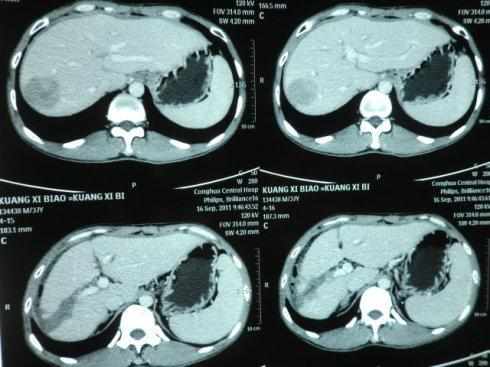

於是帶著女兒去醫院檢查,檢查結果出來後,李女士和女兒懊悔痛哭,兩人均被確診為不同程度的肝癌,住院接受治療。